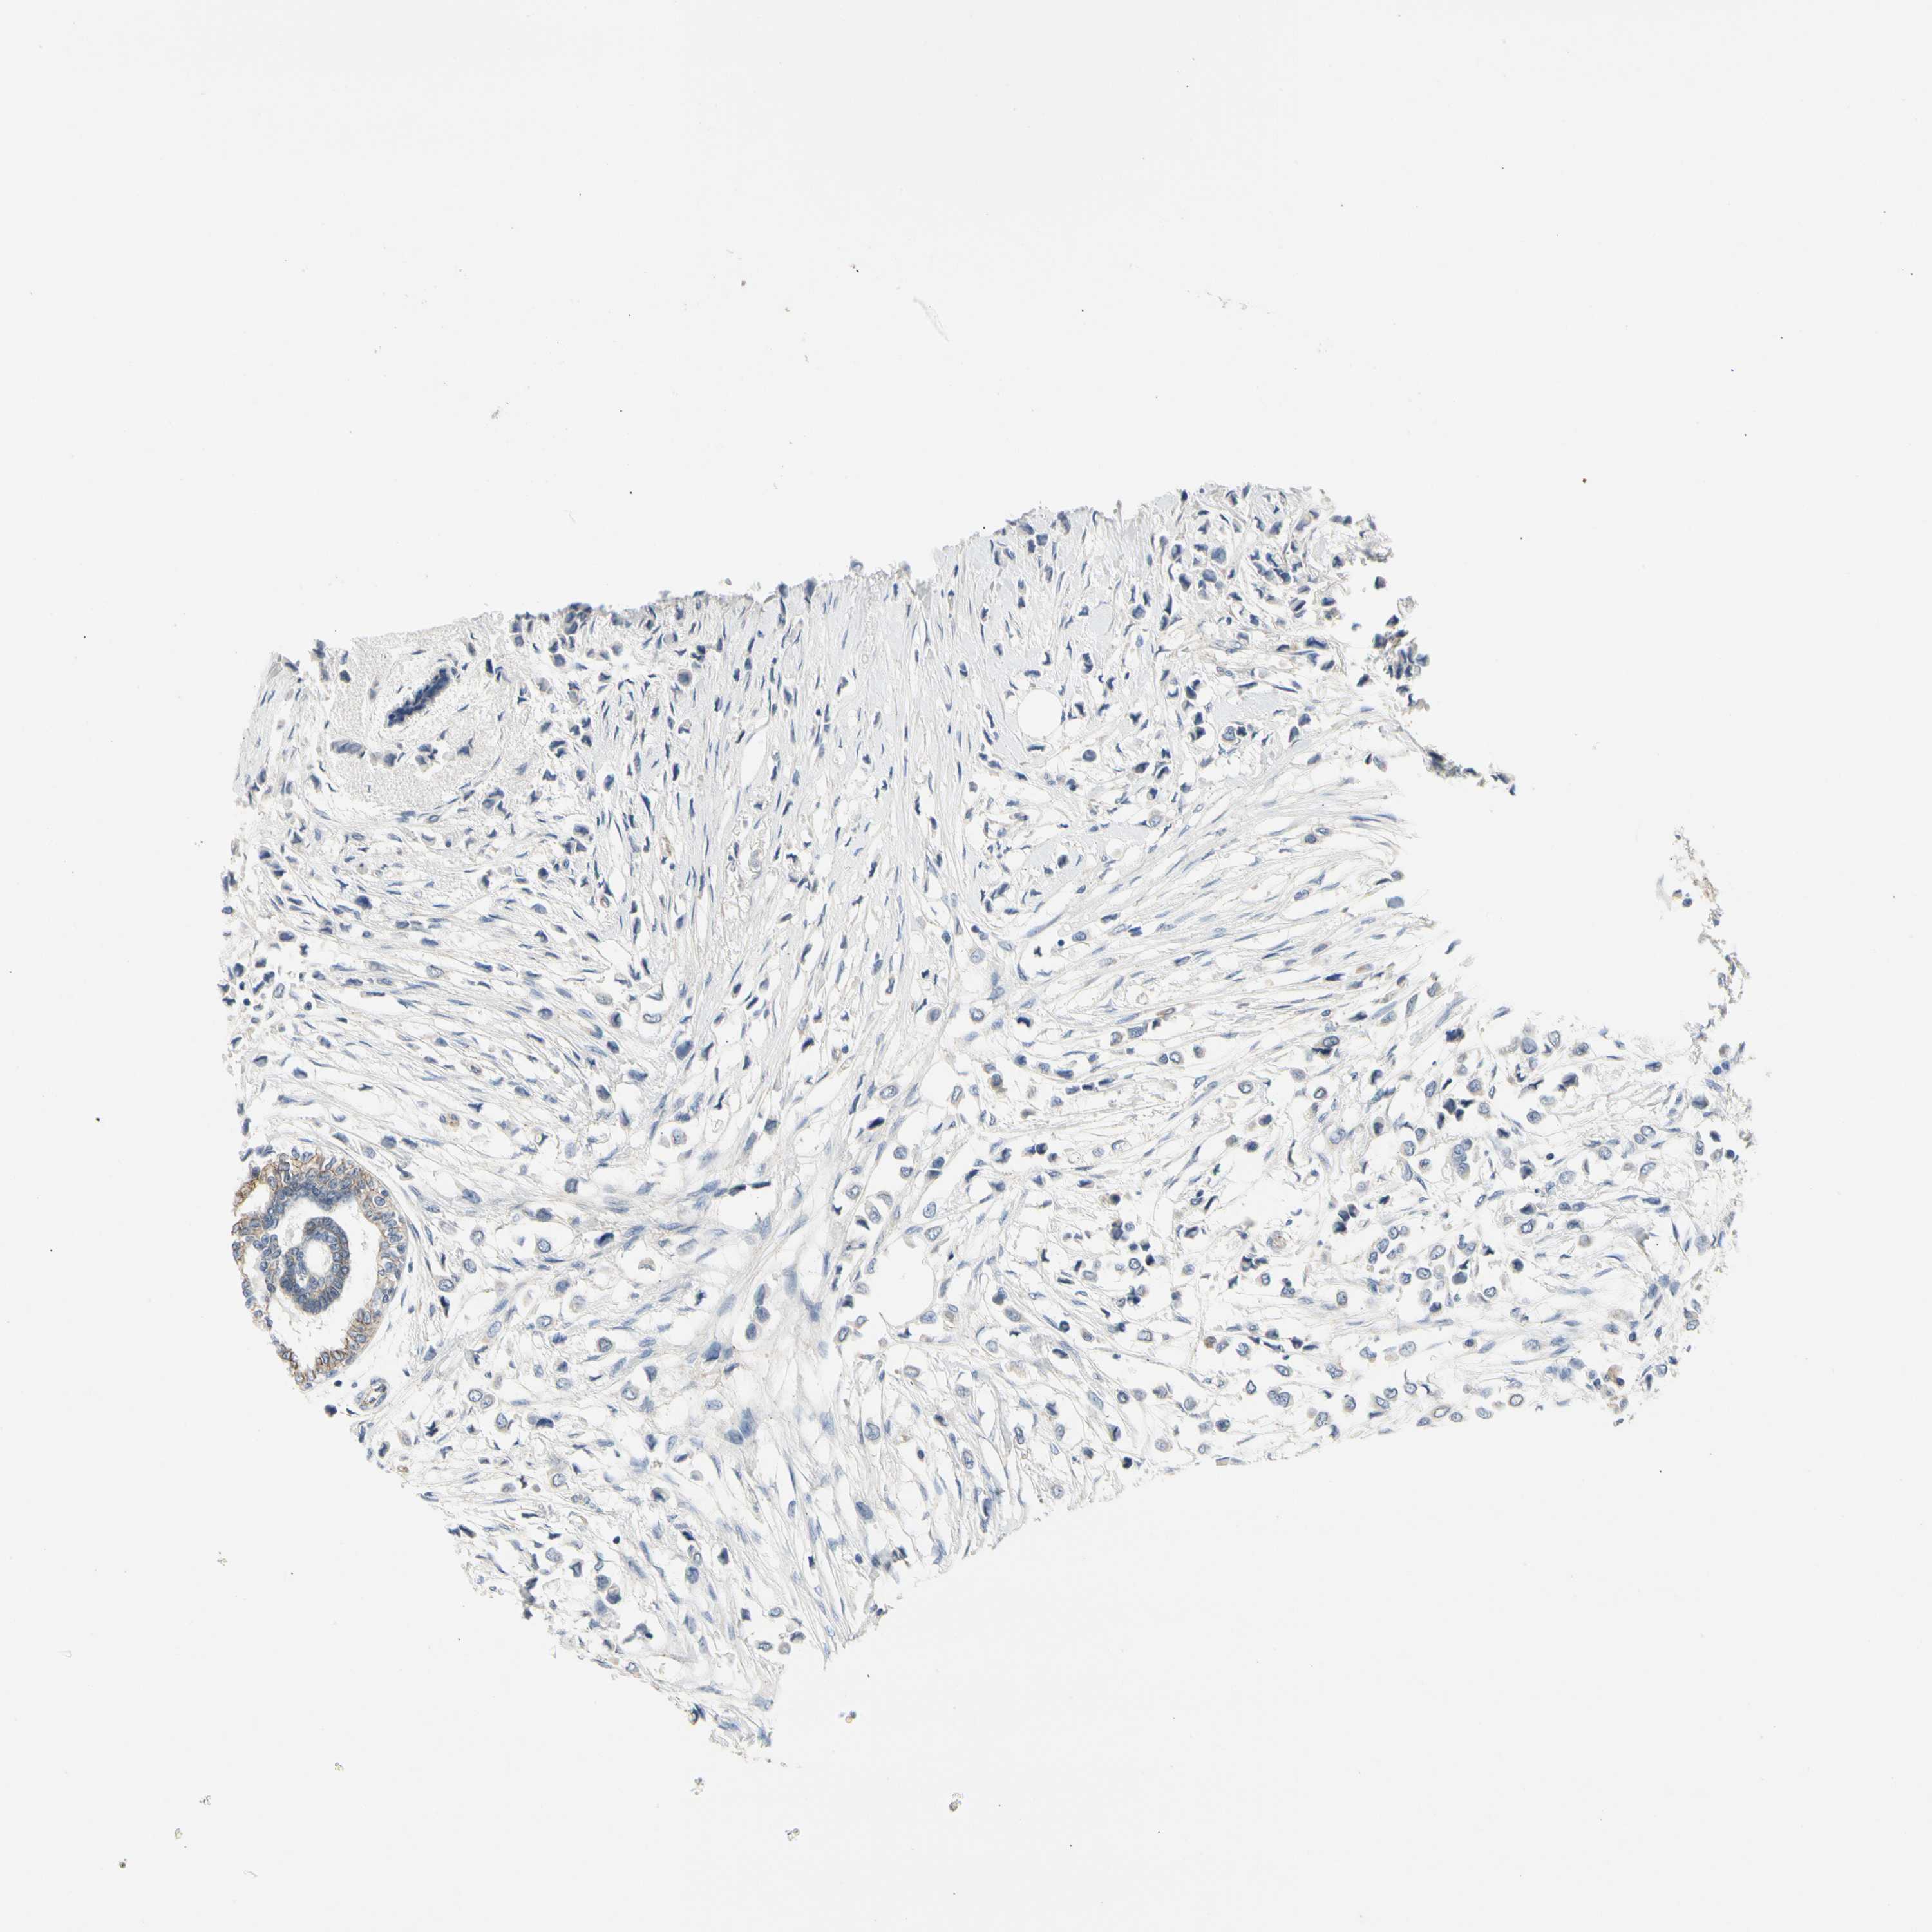

CANCER BREAST CANCER Show tissue menu

BRCA TCGA BRCA VALIDATION PROTEIN EXPRESSION

ANTIBODIES

AND

VALIDATION